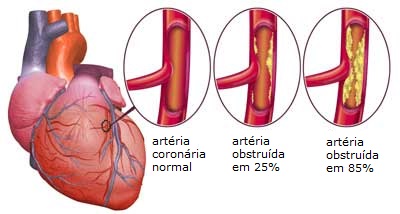

- A angina torácica ocorre quando o músculo cardíaco não recebe sangue rico em oxigênio suficiente.

- Nos homens, se manifesta por uma forte pressão no peito, podendo ir até o braço. Nas mulheres, é mais difusa. Ocorre na forma de queimadura, uma pressão indefinível, principalmente no pescoço, na mandíbula, na garganta, no abdômen, até mesmo nas costas.

- Vale ressaltar que, quando os homens sofrem de angina torácica, sentem mais dor durante a atividade física do que quando em repouso. Nas mulheres, é o contrário e pode até ocorrer durante o sono.

- Dados também mostram que problemas emocionais, tensões e ansiedade em mulheres também aumentam o risco de sofrerem este tipo de enfermidade.